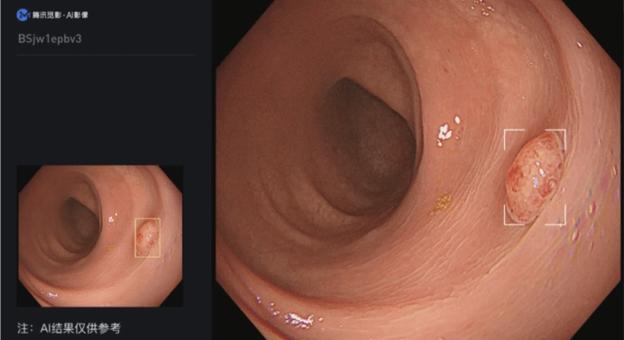

2023年6月1日,國家藥品監(jiān)督管理局發(fā)布公告,騰訊覓影旗下產品“結腸息肉電子內窺鏡圖像輔助檢測軟件”正式獲得上市批準。這一創(chuàng)新的人工智能輔助檢測產品有助于提高結腸息肉的檢出率,幫助臨床醫(yī)生更高效、準確地發(fā)現結腸息肉,從而降低結腸癌的發(fā)病率和死亡率。

“結腸息肉電子內窺鏡圖像輔助檢測軟件”需要與結腸鏡檢查配合使用。它能夠從電子內窺鏡圖像處理器輸出的視頻流中導入視頻圖像信號,并通過深度學習算法分析,實時標記出疑似息肉的位置,提醒醫(yī)生注意可能存在的病灶。